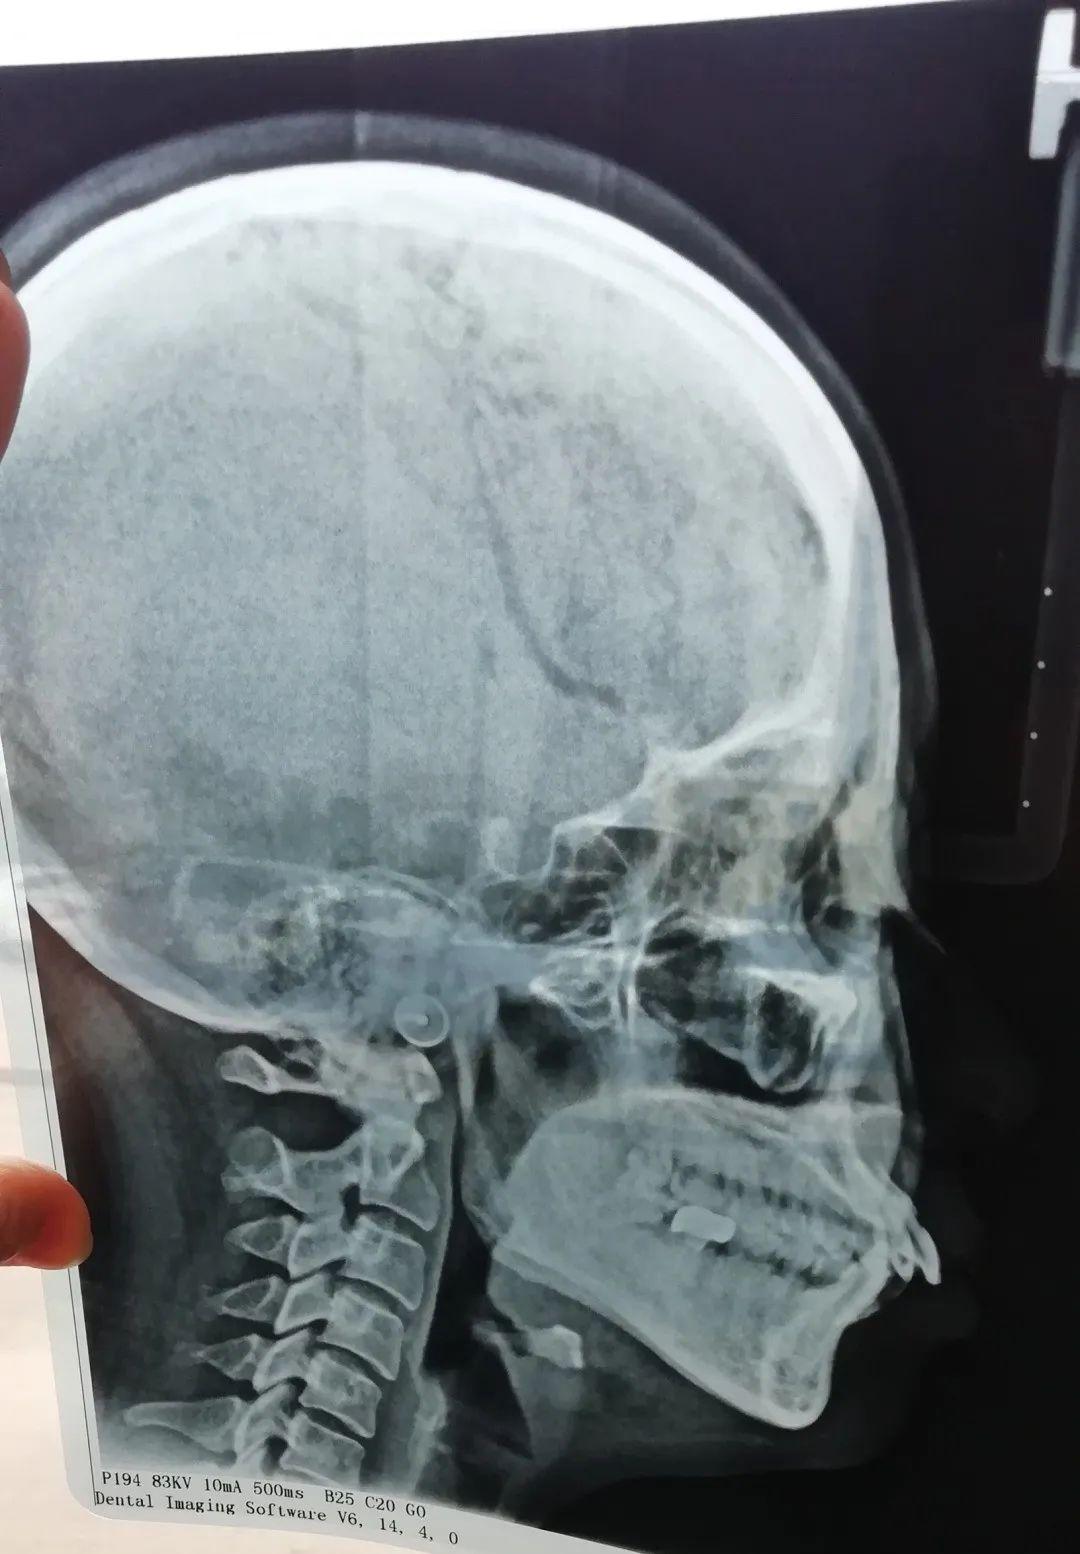

比如ct片、牙片,可以清晰的看出牙齒的問題

我拍出的片子……真是一言難盡

我不惜獻(xiàn)丑讓大家看我的牙片,正面看主要是中間牙齒的排列不齊,但從側(cè)面看簡直驚人,以前覺得我的凸嘴可能就是骨性問題,也不覺得上牙齒有多難看,看牙片就會發(fā)現(xiàn)這齙牙齙的也太離譜,不整都對不起自己。